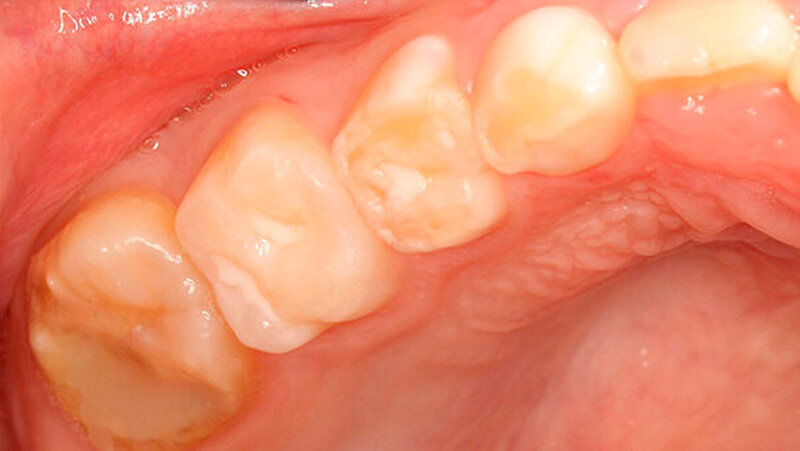

Die Patientin wies ein frühes Wechselgebiss auf, bei dem die Sechsjahr-Molaren, die gesamte Unterkieferfront und die oberen mittleren Inzisivi durchgebrochen waren. Der Zahn 54 hatte eine okklusal-distale Füllung, der Zahn 16 einen okklusal-distal-palatinalen Aufbau (Abbildung 1).

Zusätzlich zeigte der mesio-palatinale Höcker einen deutlichen Schmelzeinbruch (Abbildung 1). Die generelle Mundhygiene war nur mäßig, da insbesondere an den Glattflächen (obere mittlere Inzisivi) auch ohne Anfärbung deutlich sichtbarer Biofilm aufzufinden war (Abbildung 2). Die Zähne 26, 36 und 46 wiesen kaum sichtbare Opazitäten auf, sie waren alle versiegelt (nicht dargestellt).